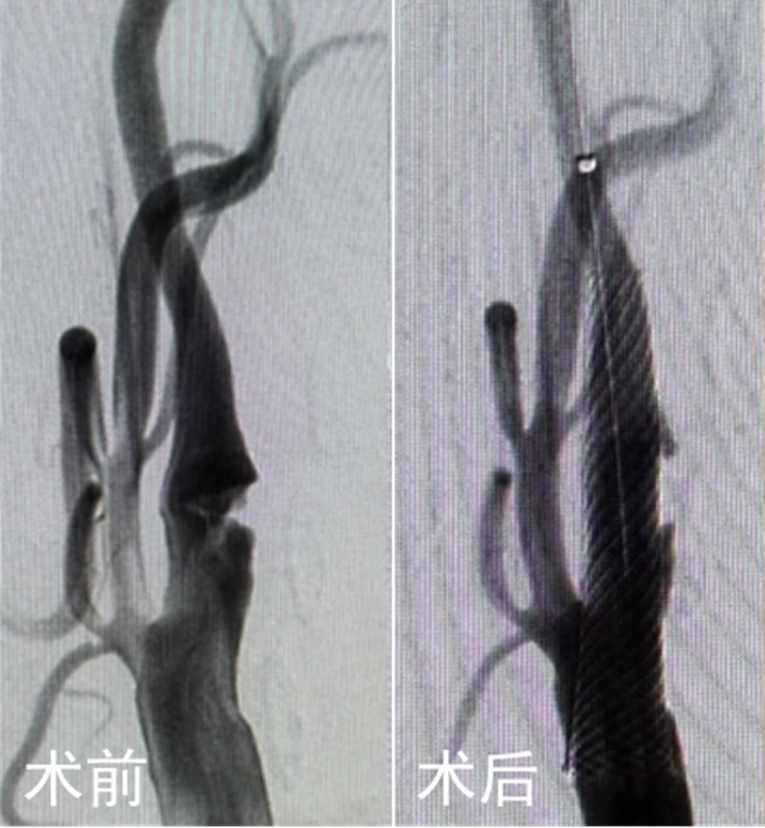

手术当天,超声医学科副主任医师夏建国对颈动脉手术区进行了精准定位。随后,赵兵和神经外科主任医师戴炯凭借娴熟的操作技巧,顺利暴露颈动脉并建立手术通路,连接血流逆转系统,在最短时间内完成了颈动脉手术治疗。术后,闵老伯感觉头晕症状明显缓解,右侧肢体麻木无力的症状未再出现。

神经外科主任医师张晓华介绍,颈动脉血运重建术直接绕过主动脉弓,利用特殊装置将血流“临时改道”,使手术时脱落的斑块碎片被直接“吸走”,不流向大脑,防止术中斑块脱落导致脑栓塞的风险,尤其适用于主动脉弓病变或有手术史的患者。